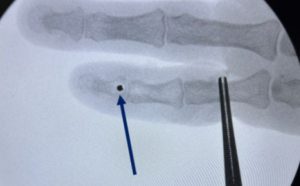

Initial reduction was achieved using Gardner–Wells skull tongs traction [5] (Fig. 5).

Figure 5: Cervical spine lateral X-ray after application of Gardner–Well tongs and successful reduction of dislocation.